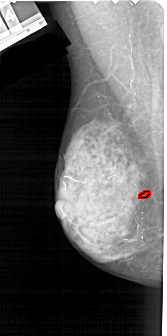

A_1223_1.RIGHT_MLO

RIGHT_CC LINES 4726 PIXELS_PER_LINE 2416 BITS_PER_PIXEL 12 RESOLUTION 43.5 NON_OVERLAY

RIGHT_MLO LINES 5281 PIXELS_PER_LINE 2491 BITS_PER_PIXEL 12 RESOLUTION 43.5 NON_OVERLAY